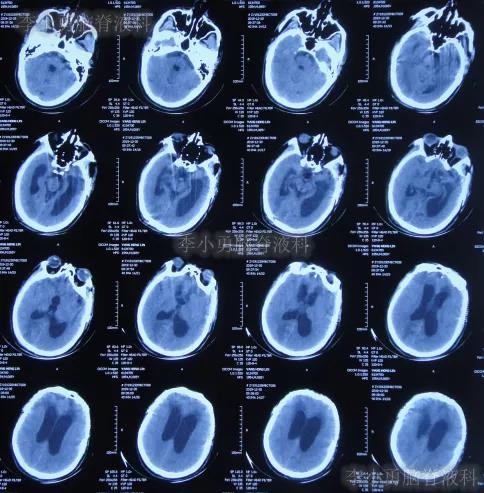

急诊进行了开颅去骨瓣血肿清除术,术后次日查头颅CT示去骨瓣术后(图-2)。

图-2:2019年10月21日头颅CT

图-3:2019年10月22日头颅CT

开颅术后第4天即2019年10月24日,查头颅CT示积血仍未明显减少(图-4)。

图-4:2019年10月24日头颅CT